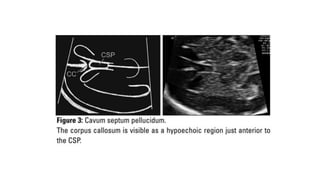

mid-sagittal image

mid-sagittal image • Thepresence of the corpus callosum can be confirmed with color Doppler of the pericallosal artery

• #16 It sits superior to the cavum septum pellucidum and extends backwards as a hypoechoic line